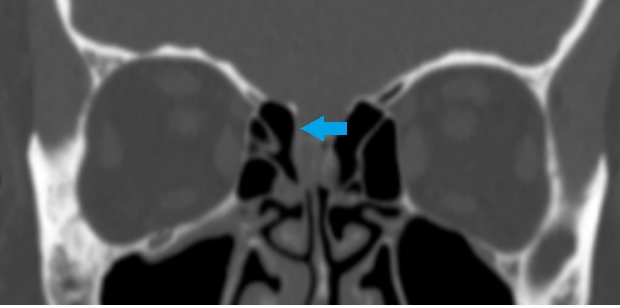

Στένωση ρινοδακρυϊκού πόρου – Ενδοσκοπική διάνοιξη (δακρυοασκορινοστομία) κατά West

Ασθενής 38 ετών με υποτροπιάζουσες φλεγμονές του δεξιού δακρυϊκού ασκού και επίμονη δακρύρροια δεξιά υποβλήθηκε σε διάνοιξη της στένωσης ενδοσκοπικά μέσω της μύτης χωρίς εξωτερικές τομές